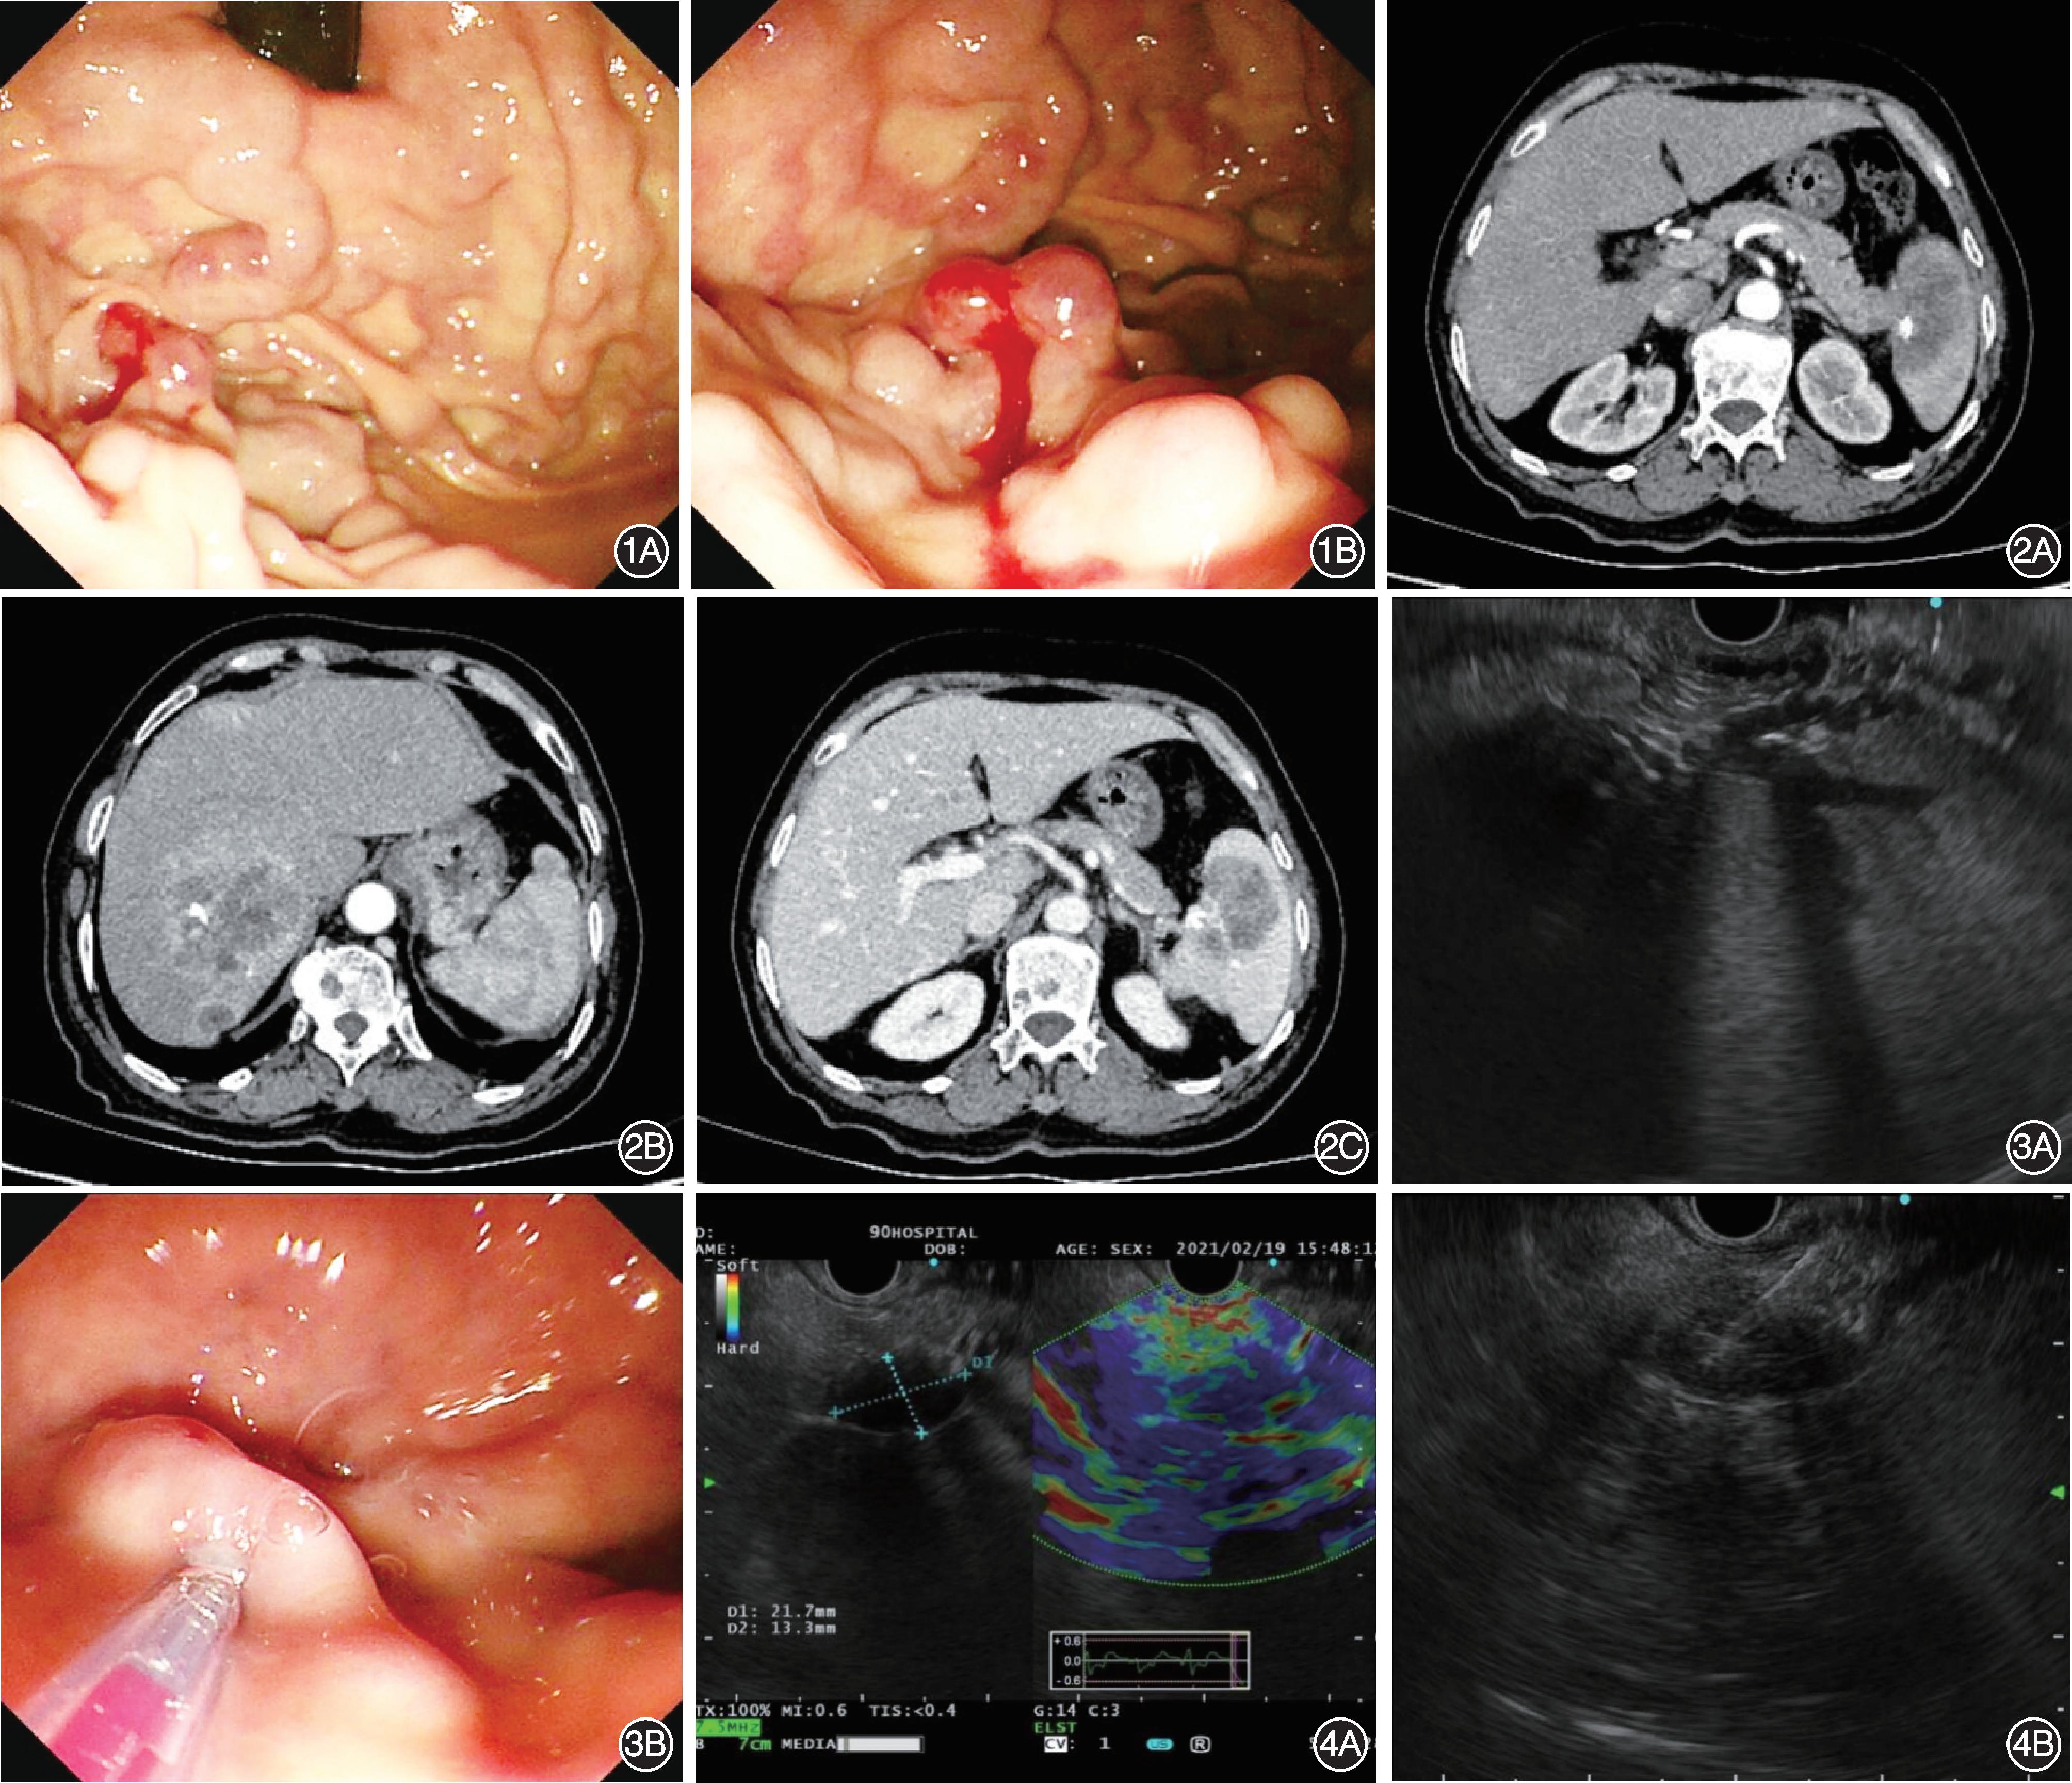

患者女,71岁,因“间断黑便伴腹痛1年,加重4 d”于2021-02-18入院。患者近1年间断性排成形黑便,伴间断性上腹痛,未进一步诊治。4天前患者再次排大量黑便(量不详),同时伴恶心、头晕、心慌、出冷汗,伴上腹痛、腰痛,无呕血。2021-02-18至我院就诊,行无痛胃镜检查示:胃底大弯见多条曲张静脉,延续至胃体中下部,最大直径0.5 cm,其中一条曲张静脉表面见小灶糜烂,表面新鲜血迹(Lg f‑b,D1.0,Rf2),未见食管静脉曲张(图1)。为进一步诊治收入我科。

既往有“高血压”病史。查体:腹平软,全腹无压痛及反跳痛,肝脾肋下未触及,移动性浊音阴性。入院后查血常规:白细胞 6.4×109/L,血红蛋白39 g/L,血小板99×109/L;凝血功能:凝血酶原时间13.3 s,凝血酶原活动度76%;肝功能:白蛋白28.1 g/L;葡萄糖 7.7 mmol/L;C反应蛋白50.3 mg/L;甲胎蛋白、癌胚抗原、糖类抗原199正常;传染病8项未见异常。腹部增强CT示:肝内多发占位(最大约7 cm×5 cm),脾脏周围、脾门及胰尾部占位,腹膜后肿大淋巴结,考虑胰腺尾部癌并多发转移瘤可能;胃底静脉曲张,脾静脉远端狭窄(图2)。

给予输血、补液、抑酸、降门静脉压力、补铁等治疗,患者病情稳定后,2021-02-19行超声内镜检查(endoscopic ultrasonography,EUS)示:胃底黏膜下见多处曲张静脉,可见穿通支静脉与黏膜下曲张静脉相延续,追踪检查见穿通支静脉来自脾门部脾静脉分支;于曲张静脉内以“三明治”法注射聚桂醇-组织胶-聚桂醇,共注射1个点位,共注射20 ml聚桂醇、1.5 ml组织胶,注射后血管变硬(图3)。

行胰腺EUS示:胰腺尾部探及一低回声占位,最大截面约21.7 mm×13.3 mm,病变与脾门分界不清,弹性成像显示质地硬,EUS引导下以22 G穿刺针穿刺病变,送组织病理学检查(图4)。病理示:送检少许胰腺组织,边缘见小灶形态较一致细胞,结合免疫组化染色结果,不排除神经内分泌肿瘤可能;免疫组化染色结果:CK(+)、Syn(+)、CK19(部分+)、β‑catenin(膜+)、S‑100(灶+)、P504s(弱+)、P16(-)、CEA(-)、CK7(-)、CgA(-)、SMAD4(-)、Ki‑67(约1%+)。术后继续给予静脉抑酸、预防感染、营养支持等治疗。经治疗后患者病情平稳,大便转黄。

图1 胃镜检查 1A:胃底见多条曲张静脉,放射样弥散分布,延续至胃体中下部,最大直径0.5 cm;1B:其中一条曲张静脉表面见小灶糜烂,表面可见新鲜血迹 图2 CT检查 2A:胰腺尾部见不规则略低密度,与脾脏病变边界不清,主胰管略扩张,脾脏内见团块状低密度,其内见片状高密度,增强扫描呈不均匀强化;2B:肝实质内见多发大小不等类圆形低密度,其内见片状钙化,增强扫描动脉期呈环形强化;2C:脾静脉远端狭窄 图3 胃底静脉曲张超声内镜检查及治疗 3A:胃底黏膜下见多处曲张静脉,可见穿通支静脉与黏膜下曲张静脉相延续,追踪检查见穿通支静脉来自脾门部脾静脉分支;3B:组织胶注射治疗 图4 胰腺超声内镜检查及超声内镜引导细针穿刺活检术 4A:胰腺尾部探及一低回声占位,最大截面约21.7 mm×13.3 mm,病变与脾门分界不清,弹性成像显示质地硬;4B:超声内镜引导下以22 G穿刺针穿刺病变